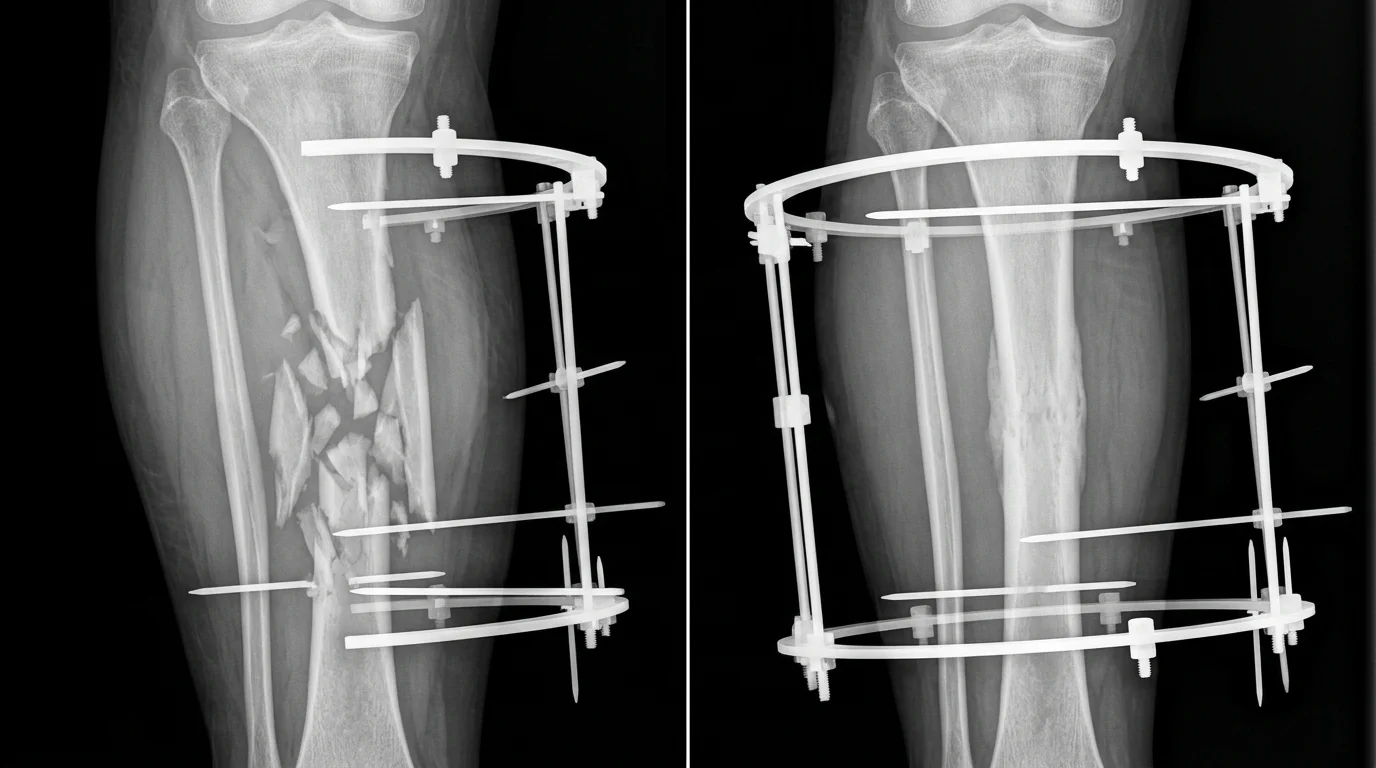

Рентгеновские снимки до и после лечения сложного перелома аппаратом Илизарова

На практике аппарат выглядит как объёмная металлическая конструкция, охватывающая конечность со всех сторон. При фиксации переломов кольца располагаются выше и ниже линии перелома, спицы проходят через кость перпендикулярно её оси, а стержни создают жёсткий каркас. При удлинении конечностей аппарат монтируется так, чтобы обеспечить управляемое растяжение тканей — спицы закрепляют проксимальный и дистальный фрагменты кости, а стержни позволяют постепенно увеличивать расстояние между кольцами на 1 мм в день. Эта универсальность конструкции — одна из главных причин, по которой российские аппараты Илизарова остаются востребованы в развивающихся странах, где требуется надёжное, универсальное и экономичное решение для ортопедической помощи.

Сложные переломы и их осложнения — первичное показание к применению. Когда традиционные методы фиксации (гипс, пластины) неэффективны, аппарат обеспечивает жёсткую стабилизацию костных фрагментов и позволяет начать ранние движения в суставах. Результаты лечения показывают сращение костей в 95–98% случаев при соблюдении протокола, с восстановлением функции конечности в течение 3–6 месяцев.

Псевдоартрозы и ложные суставы — одно из самых сложных показаний. Когда кость не срастается после перелома, эффект Илизарова достигается через контролируемое растяжение костных фрагментов и активацию регенеративных процессов. Успешность лечения составляет 85–92%, хотя сроки удлиняются до 6–12 месяцев.